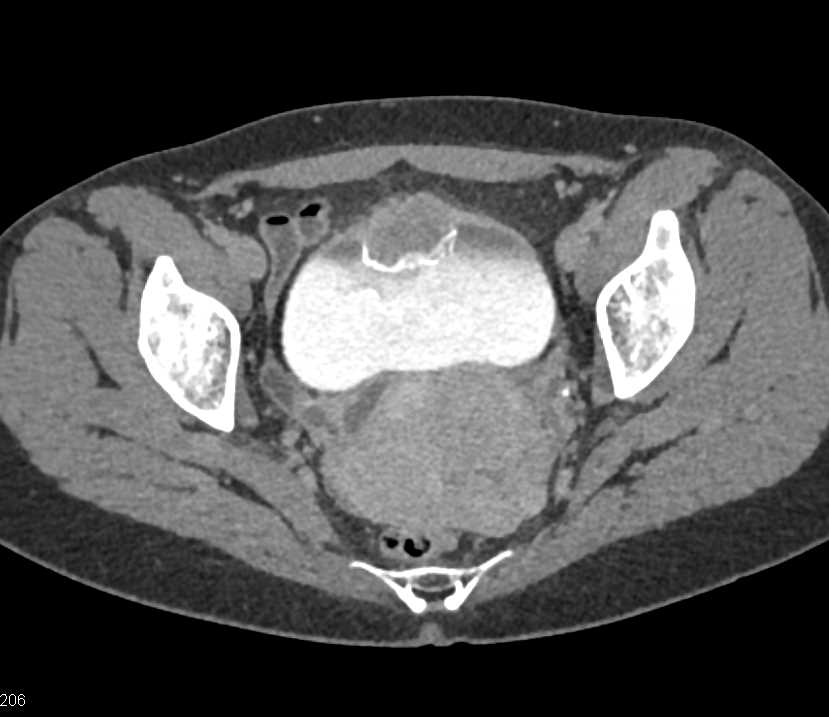

Urachal Carcinoma of the Bladder